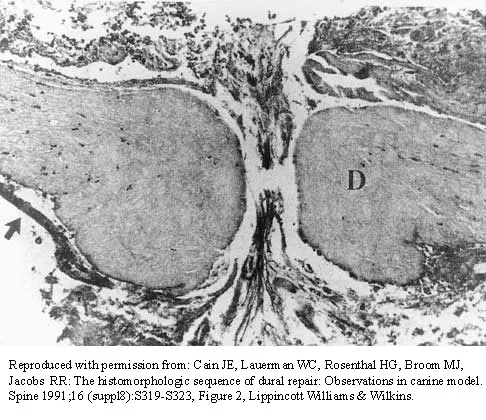

Question 90

The photomicrograph in Figure 37 shows a repaired dural tear 4 days after surgery. The material interposed between the dural edges (D) is composed of

Explanation